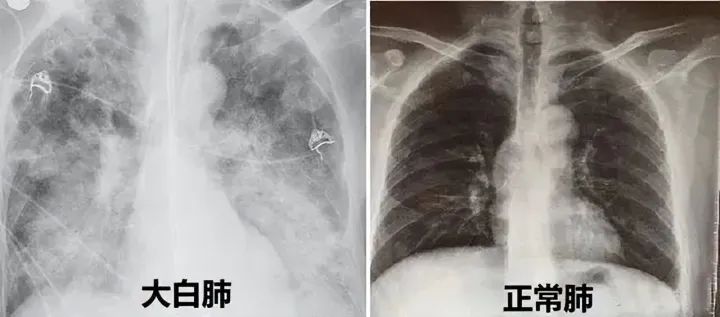

白肺

在这个就医高峰的寒冬

“白肺”逐渐成为众人议论的热词

正常情况 在X光或CT下

肺部的影相应该是 黑色的

但当肺泡里边出现炎症和感染

有渗出液和炎性细胞的时候

照出就是白色的

当这些白色区域达到

70%到80%的时候

便是临床上所说的白肺

重症白肺死亡率40%以上

高得吓人